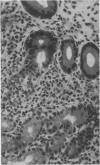

A new spiral bacterium, distinct from Campylobacter pylori, was found in the gastric mucosa of six patients with gastrointestinal symptoms. All patients had chronic active type B gastritis and four had oesophagitis. Culture and microscopy for C pylori infection was negative. These unculturable spiral organisms were probably an incidental finding in patients presenting for upper gastrointestinal endoscopy, but it is not possible to say from this small series whether these organisms cause chronic active gastritis. The organism is helical, 3.5-7.5 microns long and 0.9 micron in diameter with truncated ends flattened at the tips, and up to 12 sheathed flagella 28 nm in diameter at each pole. It is proposed that this spiral bacterium should be called "Gastrospirillum hominis Gen.nov., Sp.nov."